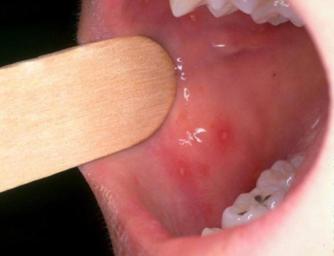

7.手足口病

手足口病是由肠道病毒引起的传染性疾病,3岁以下年龄组发病率最高。临床主要表现为口腔或咽喉痛,或者拒食。若存在发热,通常小于38.3℃。

皮疹特点:皮疹开始为斑疹,逐渐进展为水疱,水疱破裂形成浅表溃疡,且通常累及双手、双足、臀部(特别是在婴儿及幼儿中)及四肢。口腔病损为痛性,可能妨碍经口摄食(图11、图12)。皮肤病损为非瘙痒性且无触痛(图13)。